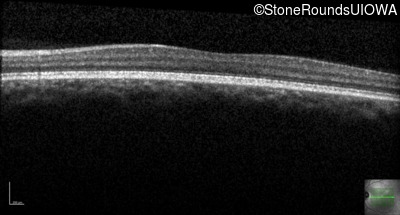

Congenital Stationary Synaptic Dysfunction (IA2g)

Congenital Stationary Synaptic Dysfunction (IA2g)

| Congenital Stationary Synaptic Dysfunction | CABP4 | Arg49Stop CGA>TGA | IVS1+1 G>T | AR |